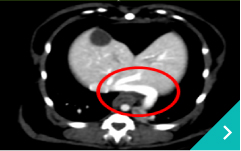

IVRとは、レントゲン透視(X線)や超音波などの画像を使いながら、カテーテルという細い管を体内に通して、病気のある部位を治療する方法です。開胸や開腹をせずに治療できることから、体への負担が少なく、多くのわんちゃん・ねこちゃんにとって優しい選択肢となります。

門脈体循環シャント:異常な血管にコイルやプラグを入れて、血流を正常化します。